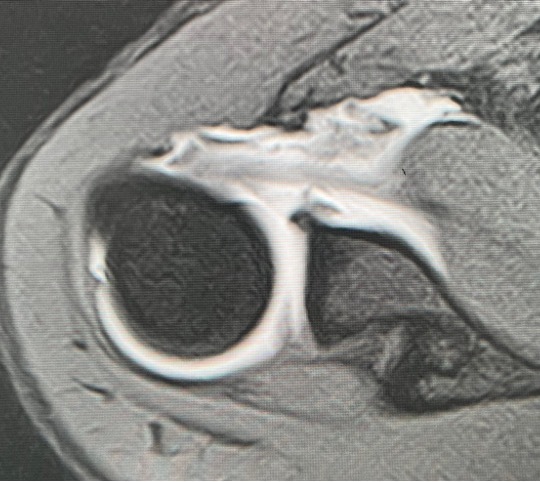

上方関節唇損傷(Superior Labrum Anterior and Posterior lesion、以下SLAP損傷)は野球やバレーボールなどのオーバーヘッドスポーツに多く起こる障害です。繰り返しの投球動作による反復動作により、上腕二頭筋関節唇複合体に負荷がかかり上方関節唇が関節窩から剥がれてしまう状態です。また投球動作の反復だけでなく、スライディング動作で腕を伸ばして手をついた際に受傷したりする場合もあります。自覚症状としては、投球動作時(レイトコッキング期に多い)の痛み、引っ掛かり感、不安定感などがあります。

投球動作におけるレイトコッキング期に肩が外転―外旋位に強制された際、上腕二頭筋腱に捻れが生じ、その付着部である上腕二頭筋関節唇複合体にも捻れ+牽引ストレスが加わり(Peel bach mechanisim)上方関節唇の剥離が生じます。

投球動作におけるレイトコッキング期に肩が外転―外旋位に強制された際、上腕二頭筋関節唇複合体が腱板(肩のインナーマッスル)に挟まれる状態(インターナルインピンジ)になり、関節唇の剥離が生じます。